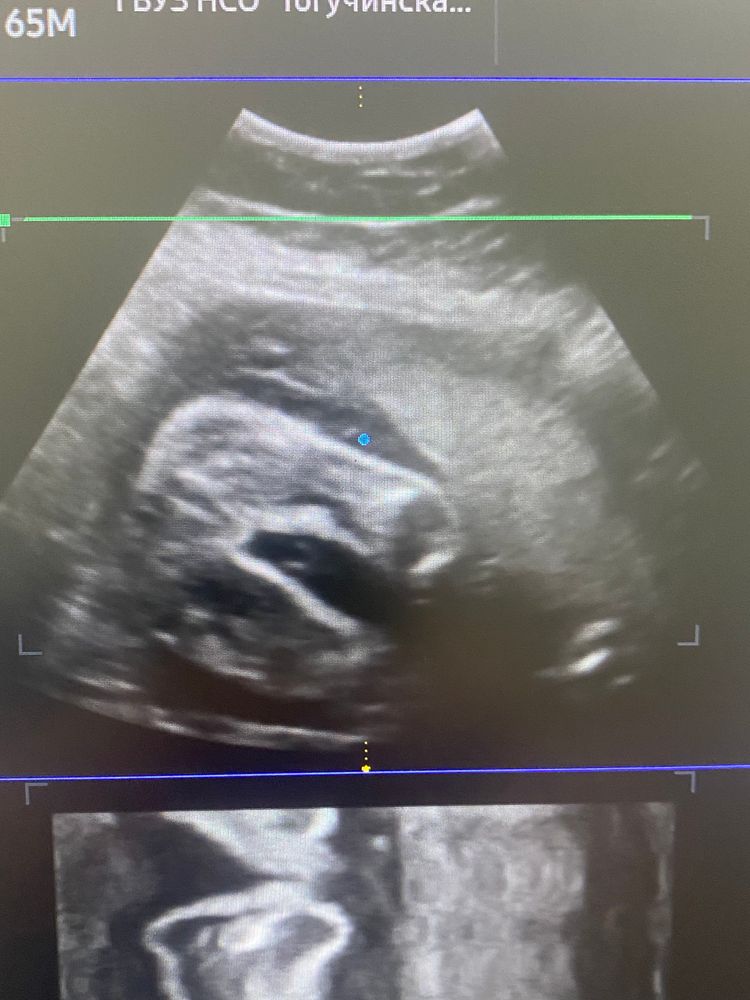

Девочки подскажите кто все таки по узи будет мальчик или девочка?

Девочка, у мальчика между ножек еще деталь есть😀